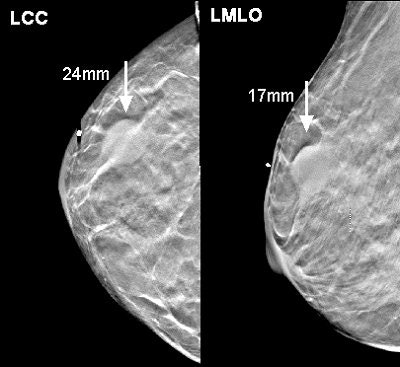

![]() |

| Above, a DBT study in CC and MLO view with a dramatic lesion. Below, DBT study in CC view with two lesions at two different levels. Images courtesy of Dr. Laurie Fajardo, Breast Imaging Research, University of Iowa, Iowa City. |